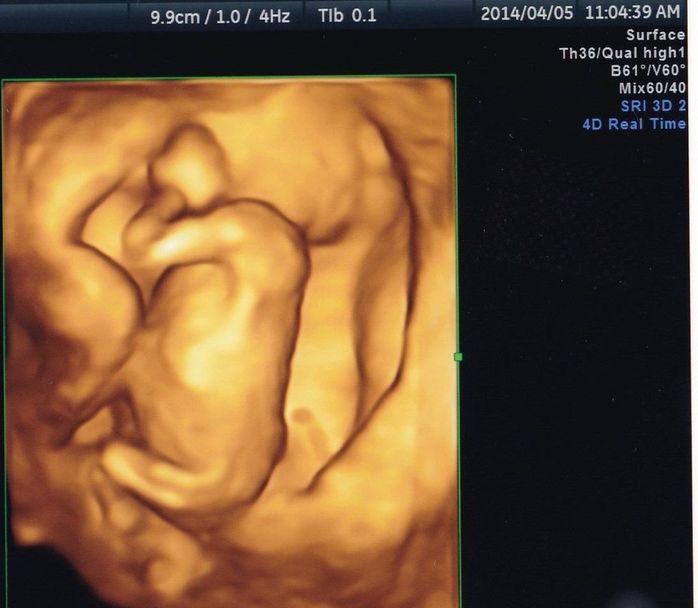

妊娠14週目の4Dエコー写真 初めての4Dのリアル画像にびっくり

D=10.2cm

この検診から4Dエコーでの診断になります。左を向いて、手と足を曲げて赤ちゃんらしい姿が映し出されました。4Dの映像はリアルで、こんなに小さくても手や足がしっかりついていることに生命の神秘を感じました。私もおなかのふくらみを感じるようになり、少しゆるめの服装で過ごすように。軽い風邪をひいたり、肌荒れがひどくなったり、マイナートラブルが目立ってきて、不安を感じることも多かったです。